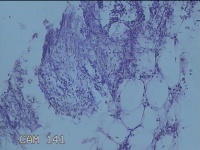

右侧会阴部结节

性别

女

年龄

31岁

临床诊断

皮脂腺囊肿

一般病史

发现右侧会阴部结节2个月。

标本名称

大体所见

灰白暗红色结节1.7x1.3x0.3cm一个,表面糜烂,切开结节呈实性,切面灰白暗红色,质软。

图1

炎症性病变。